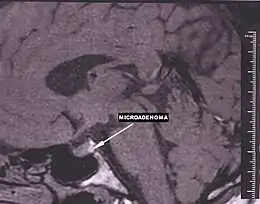

En estudios realizados mediante análisis de series de autopsias y estudios de imagen, se ha comprobado que la existencia de tumores hipofisarios es muy frecuente, presentándose en alrededor del 16.7 % de la población. La mayor parte de ellos son de pequeño tamaño (microadenomas) y no producen sintomatología, descubriéndose de forma casual.[3]